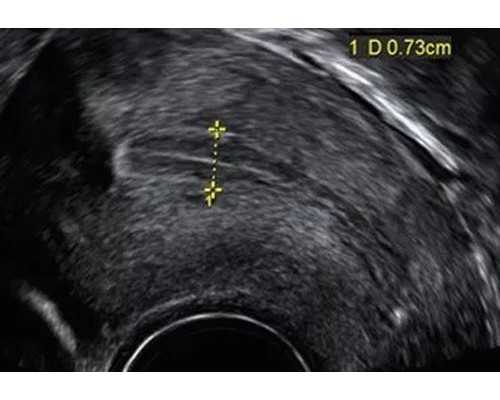

香港DNA的染色体检查,原理根据怀孕妈妈血液中胎儿游离DNA片段来鉴定肚子里孩子的性别,要到医院做B超,然后确定怀孕时间是不是7周以上,胚芽十个毫米,然后抽取怀孕妈妈的血液进行检测了,费用不是很贵,技术是抽取怀孕妈妈手臂静脉血液

1、提醒妈妈一定要提供确保医生注明满6周以上的B超单并携带过来香港,以确保准确率及避免不必要的麻烦。

香港抽血 ,香港检测 ,受测者提前准备好港澳通行证或者护照,受测者在当地医院做B超确定胎龄在7周以上,并携带B超报告单带过来,提前预约好受测者到香港抽血的时间,专业人员陪同受测者到香港抽血

1. 最早:在B超确认胎龄在7周以上就可以鉴定,让准父母最早为宝宝做准备。

2. 最安全:只是抽取母体12毫升静脉血就可以做鉴定,对孕妇无伤害无痛楚。